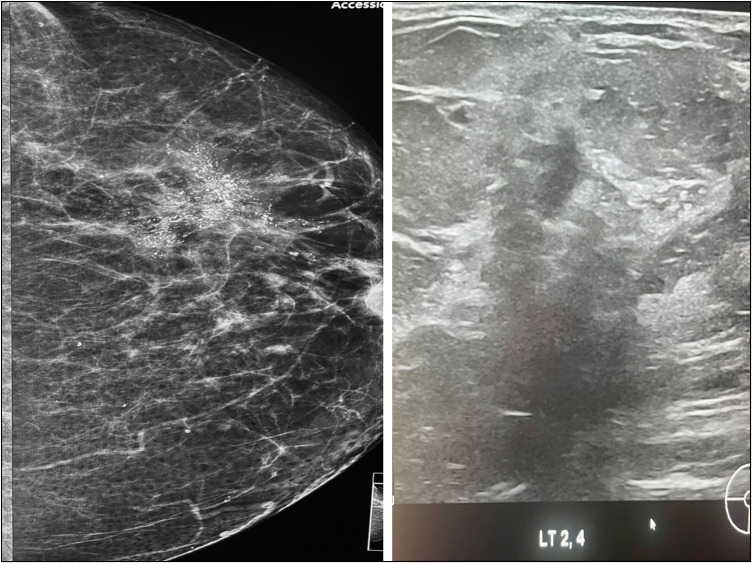

Background: Approximately 80% of ductal carcinoma in situ (DCIS) cases are asymptomatic and manifest as microcalcifications, usually detected on screening mammograms. Stereotactic biopsy is used as the primary modality for histopathologic diagnosis. Ultrasonography has been relied upon as a potentially viable alternative for early breast cancer detection, especially in low- and medium-income countries.

Results: Eighty women included were within the age range of 46-79 years, with mean age of 60 years. Background breast density was predominantly fatty in 51/80 (63.8%), without any correlation with mammographic abnormalities. Microcalcifications were classified as indeterminate (M3) in 42/80 (52.5%), while suspicious (M4) and malignant (M5) types were seen in 38/80 (47.5%). No targeted sonographic abnormalities were noted in 69 (86.2%) of the patients, while 11 (13.8%) had sonographic abnormalities. The predominant sonographic feature was non-mass hypoechogenicity in 6/11(55%). There was a correlation between mammographic code, lesion size, and ultrasonic abnormality, with 9/11 (81.8%) patients with sonographic lesions having suspicious and malignant type calcifications. The mean mammographic lesion size was significantly greater in women with abnormal ultrasound findings, 42 vs. 20 mm. Histological tumour grade was high grade in 10/11 (90.9%) lesions.

Conclusion: The accuracy of breast ultrasonography as an adjunct in the detection of screen-detected microcalcifications and subsequent guided biopsy is higher when dealing with malignant type microcalcifications >15 mm in size.